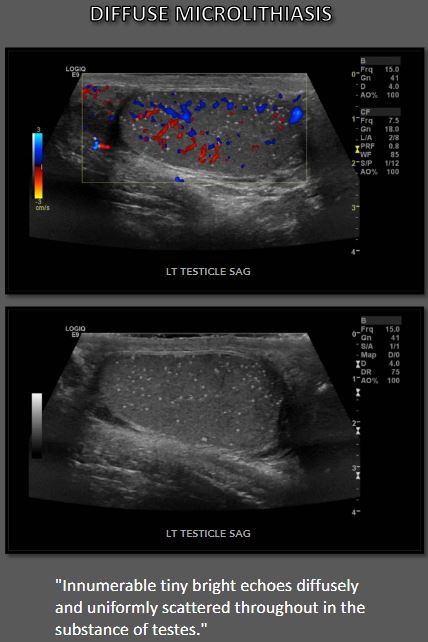

첫 번째 초음파 설명은 다음과 같습니다. 1987년에 “무수한 작은 밝은 메아리가 확산되고 균일하게 울립니다. 물질 전체에 흩어져 고환의.” 그 이후로 많은 수의 다양한 설명과 정의 를 설정하는 데 사용되었습니다. 고환 미세 결석 진단. 가장 보편적으로 받아들여지는 정의는 5개 이상을 포함합니다. 단일 필드당 관찰되는 미세석 초음파에서 보기(이미지). 미세석 현재 상태와 관련된 작고 같은 크기(<3mm) 에코 발생 후방 그림자가 없는 초점 고환 전체에서 관찰됩니다. 고전적인 초음파이지만 고환 미세 결석증의 발현 확산, 마이크로리스는 고환의 일부가 보고되었습니다.

반짝이는 인공물은 평가할 때 볼 고환 미세 결석 컬러 도플러 초음파. 마이크로리스의 수 이미징에서 감지된 내용은 다를 수 있습니다. 상당히. 조건 로 등급이 매겨졌다 최소/약함(등급 I: 5~10 microliths), 중간 (등급 II: 10 내지 20 마이크로리스), 및 중증(등급 III: >20 마이크로리스)에 따라 미세 석회화 수 단일 보기에서 볼 수 있습니다.